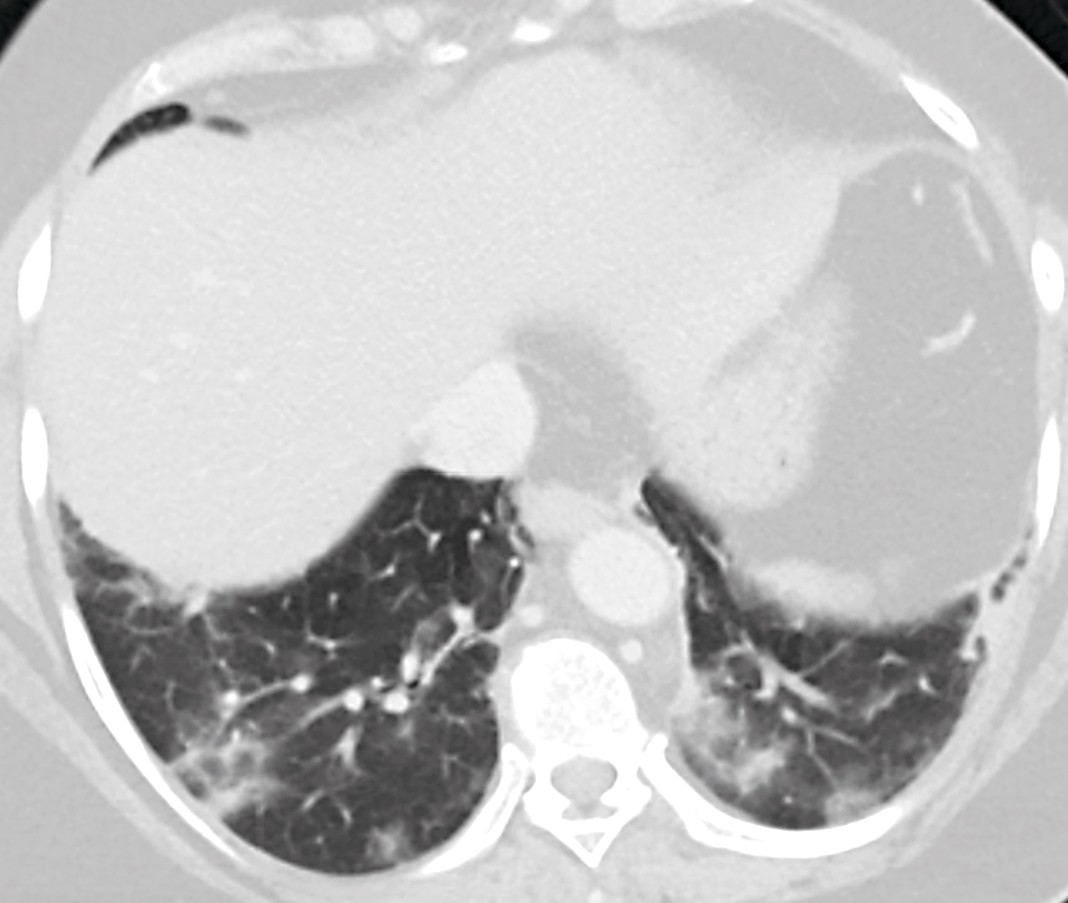

An ultrasound examination of the liver and biliary tract was requested. However, as the patient was overweight, and several radiologists were in quarantine due to the ongoing corona epidemic, it was decided to do a CT scan with intravenous contrast instead. The CT images of the abdomen showed no relevant findings in the abdomen, except gallstones that were previously known. There were no radiological signs of cholecystitis. However, cross-sectional images of the lower thorax showed peripherally diffuse opacities in both lungs as well as some areas with a more consolidated appearance. There were no signs of pleural effusion. The radiologist suspected viral or atypical pneumonia (Figure 1).

Figure 1 Cross-sectional image of the bases of the lungs as part of the CT examination of the abdomen. The image shows…

Figure 1 Cross-sectional image of the bases of the lungs as part of the CT examination of the abdomen. The image shows peripheral, patchy bilateral ground glass opacity with elements of consolidation.